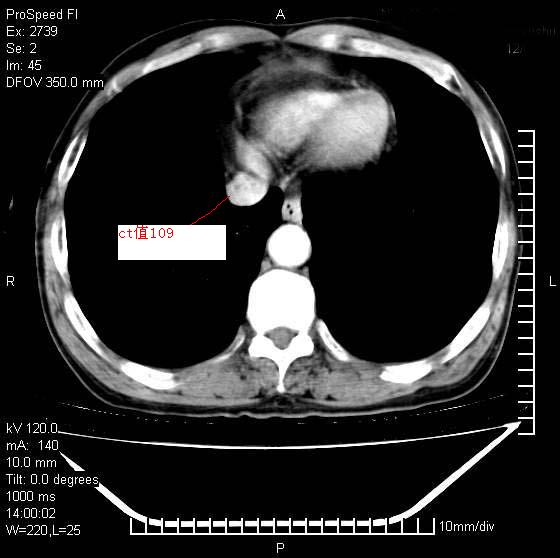

以下是引用andymaomao在2007-12-7 15:54:00的发言:[br]1.双上肺陈旧肺tb灶;[br]2.双中上肺矽肺;[br]3.双肺气肿;[br]4.图中箭头所指乃下腔静脉。

以下是引用山之魂海之韵在2007-12-7 18:59:00的发言:[br]支持矽肺,左肺上叶陈旧性结核,肺气肿。箭头所指乃下腔静脉。下腔静脉显影比主动脉显影迟,增强动脉后迟可以是不均匀的。

以下是引用chengjiaqiu1在2007-12-7 17:49:00的发言:[br]矽肺,左肺上叶陈旧性结核,肺气肿。中箭头所指乃下腔静脉。